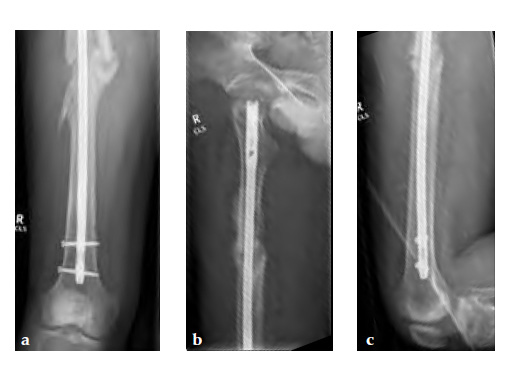

Insertion of A2FN as patient may be suffering from a stress fracture related to long term (2.5 years) bisphosphonate use. My rationale against a plate is because bisphosphonate related fractures will heal extremely slowly. In our experience even despite bone grafting union may need up to 2 years. In that time, a plate will fail in less than a year even if the patient is only allowed very minimal weight bearing.

Note despite the increased in curvature compared to other nails in the market, there is still noticeable malreduction at the fracture site (see Fig 6a-b).

Patient was allowed and achieved immediate weight bearing and in 6 weeks callus is seen at the fracture site (see Fig 7a-b).